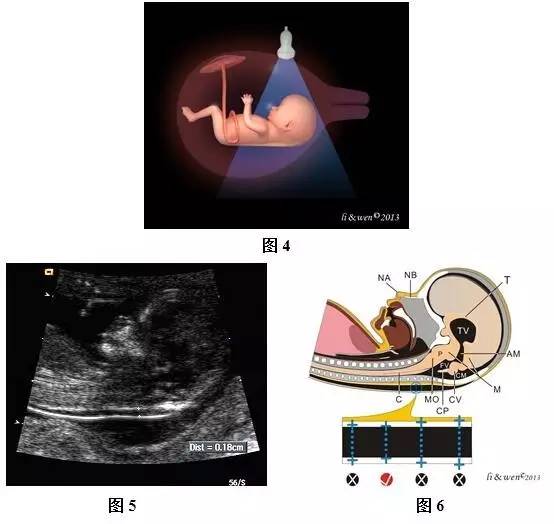

超声扫查方法:声束通过胎儿间脑、菱脑、鼻骨、鼻尖、颏部、脊髓等作正中矢状切面扫查。扫查时尽可能将图像放大,使图像只显示胎儿头颈部及上半胸,获取胎儿头颈部及上半胸的正中矢状切面(图4~6)。

标准切面判断标准:此切面上可清楚观察到NT、间脑、菱脑、鼻骨、鼻尖、颏部、脊髓等。NT应尽可能在图像上呈水平位,清楚显示并确认胎儿背部皮肤(而非羊膜),胎儿处于自然伸展姿势。

主要观察内容及测量要求:测量NT厚度时应在NT的最宽处测量垂直于NT无回声的距离,测量游标的内缘应置于无回声的NT的外缘,使测量游标的轻微移动只会改变测量结果0.1 mm,并在胎儿自然姿势(无过屈或过伸)时测量NT厚度;应测量多次,并记录测量所得的最大数值。有颈部脑脊膜膨出、颈部脐带时,注意辨认,避免误测。有颈部脐带时,NT测量应分别测量颈部压迹上、下两端最宽处的距离,并取两者的平均值。

图4~6孕12+2周胎儿NT值测量扫查模式图及声像图。图4胎儿NT扫查模式图;

图5、6胎儿NT测量声像图;图6胎儿NT测量模式图,图下方显示测量游标放置的部位,√表示测量正确,×表示测量错误